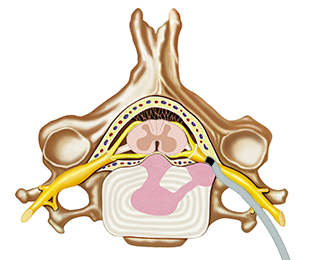

신경성형술(PEN) 치료과정

신경성형술 치료는 국소마취로 부담이 적고, 환자와 대화를 하면서 시술을 진행하여 안정적인 편입니다. 치료를 시행할 때는 약물을 정확한 위치에 투여하는 것이 중요하기 때문에 C-ARM 촬영을 함께 진행하고 있습니다.

1단계

국소마취 후 실시간으로 치료부위를 확인하면서 옆구리 혹은 꼬리뼈를 경유하여 카테터를 삽입합니다.

신경성형술(PEN) 염증제거 과정

01

신경이 유착되고 염증이 가득차 통증 발생

02

카테터로 접근하여 신경의 유착을 풀어줌